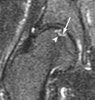

골괴사가 의심되지만 X-ray 소견이 정상이면 MRI를 해야 합니다(괴사가 생기고 3~4주 후에야 MRI상 이상 소견이 관찰됩니다). 한쪽의 비외상성 골괴사 환자에서 MRI 결과 증상이 없는 반대쪽에서 초기 골괴사가 발견되면 상태가 진행되기 전에 수술을 합니다.

1. T1 weighted image

1) Hypointense peripheral band : reactive interface

2) ±Hypointense bone marrow edema & joint effusion

3) Subchondral changes in antero-superior quadrant of head with single line density, demarcating normal from ischemic bone

2. T2 weighted image

1) Characterstic ‘double line’ sign in 80%

2) High signal line inside a low signal line(double-line sign)